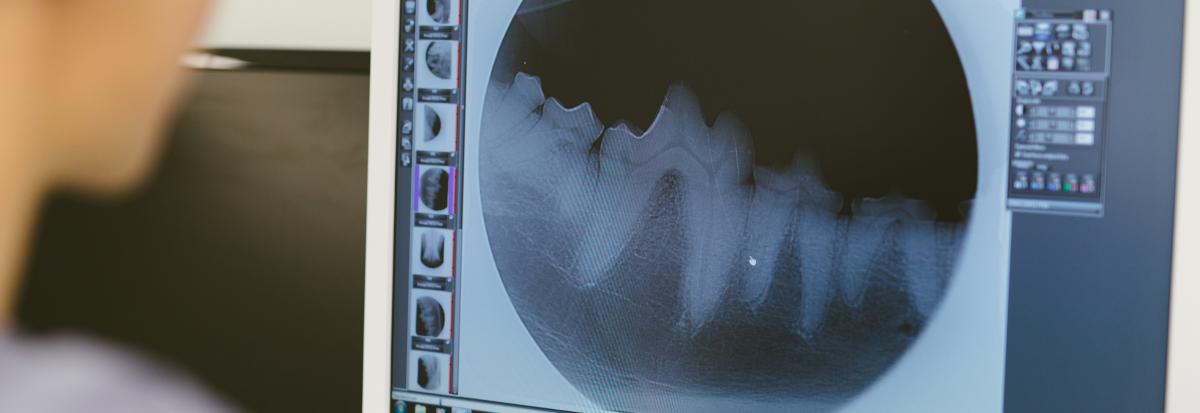

Vuosien mittaan klinikan toiminta laajeni, nimikin vaihtui Aveciksi ja klinikalla alettiin tarjota palveluita, joita alueen muilta klinikoilta ei ollut saatavilla. Tässä vaiheessa Chita alkoi perehtyä lemmikkien hammashoitoihin, jotka työllistävätkin hänet nykyään lähes kokonaan.